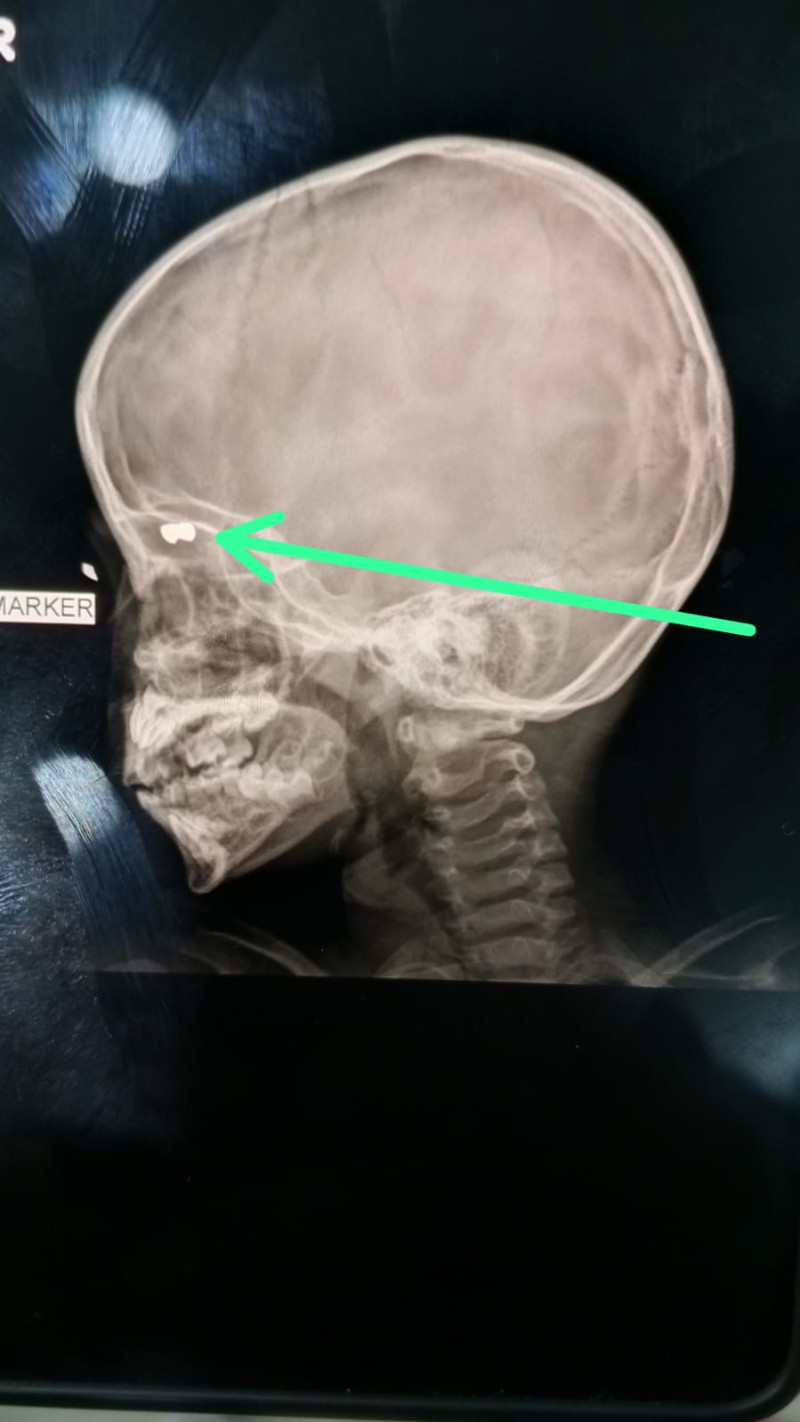

Wanita itu sedang menunggui anaknya yang masih berusia 4 tahun, sedang dalam perawatan karena pelipis mata kanannya tertembus peluru nyasar senapan angin.Romanda menyebut, saat ini kondisi anaknya sangat memprihatikan. "Mau sampai kapan dia kayak gini. Setiap dia nangis, dari mata itu keluar darah," lirih Romanda kepada wartawan.

"Tolonglah dibantu supaya anak saya ini bisa dikeluarkan pelurunya," harapnya.Penuturan Romanda, nahas itu terjadi ketika bersama korban menaiki becak. Di Tempat Kejadian Perkara (TKP) sedang terjadi tawuran Kampung Kolam dengan Kampung Kurnia pada Senin (5/1/2026) siang.